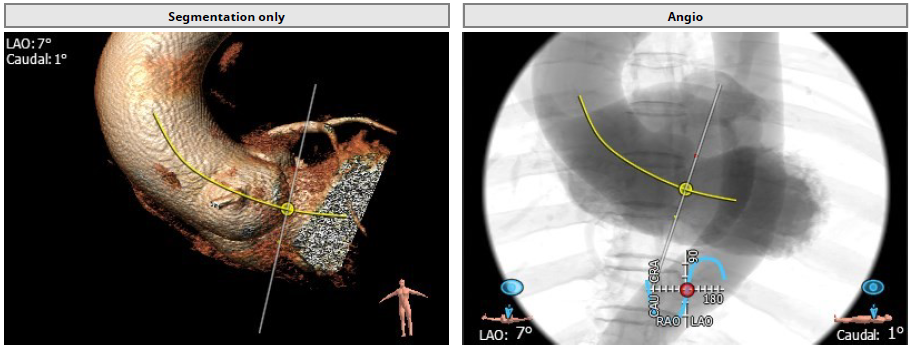

4.患者术中造影角度LAO:7°,CAU:1°。

Annulus: 30.1mm

环上结构折算直径:30.3mm ;主动脉瓣环夹角:135°

左冠高度:16.2mm;右冠高度:21.8mm

LVOT: 31.5mm;窦部直径:42.7/42.0/46.9mm

窦管交界:39.9mm;升主动脉:44mm

术中造影角度LAO: 7°,Caudal: 1°